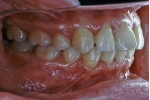

| 初診時